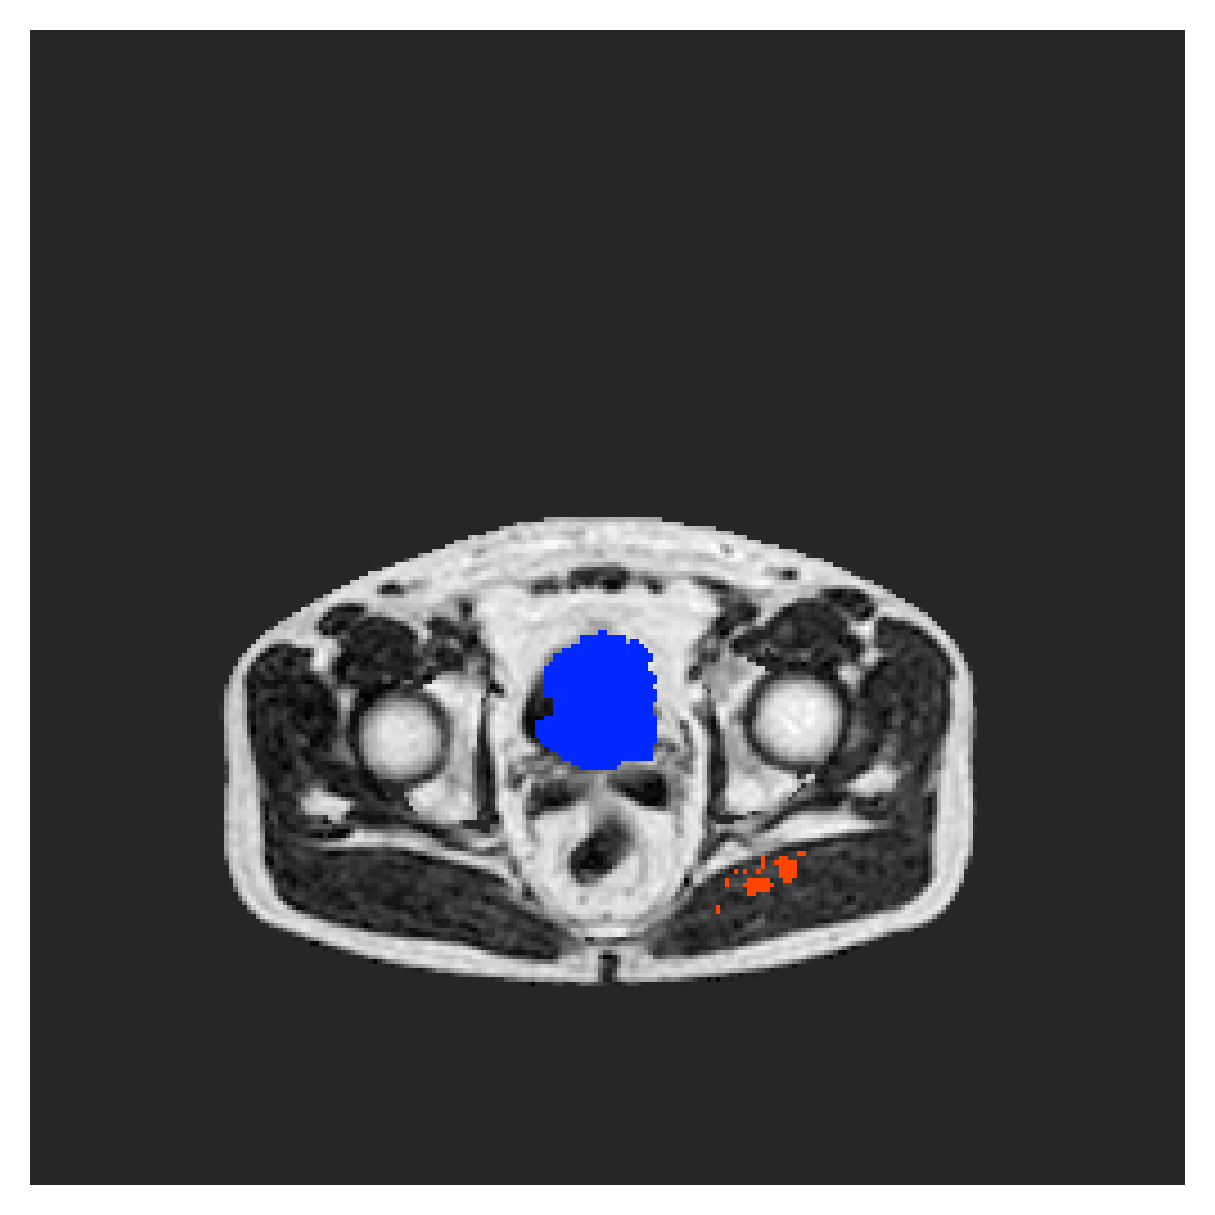

POEM

The Prospective investigation of Obesity, ENergy production and Metabolism (POEM) is a local (not currently publicly available; PI: L. Lind, see [22] for details) cohort of whole-body fat/water separated MR images. Full annotations of the liver, kidneys, bladder, pancreas and spleen are available for 50 subjects, providing a challenging segmentation dataset with heavily imbalanced classes of varying shapes. The resolution of the data is anisotropic, with reconstructed voxel size of in left-right, anterior-posterior and foot-head directions, respectively. For additional technical details regarding the acquisition and specifications of the images see [22].

The images contain two channels, one for water and one for fat content. For training, we normalize the volumes (per channel) and use 2D slices in the coronal plane, sized . The weak annotations are created synthetically, following the same procedure as described for the ACDC dataset.

5.2 Abdominal organ segmentation

Using 2D distance maps

In Table 3, the average DSC and HD95 results are shown (both using 2D and 3D distance maps) for the task of abdominal organ segmentation in POEM data (for boxplots see figures 8 and 9). We see that training with and (with distances calculated on 2D slices) performs comparably, while using and produces lower scores in both DSC and HD95 metric. On this dataset, the CRF-loss is able to compete with the boundary loss-based training strategies, even outperforming them on most classes. Most notably, all models trained with boundary loss appear to have a hard time segmenting the liver. We hypothesize this may be due to extremely severe class imbalance, as the liver covers a very large area compared to the rest of the classes. It is thus also more strongly affected by undersegmentations.

5.2.1 Qualitative comparison

In Figure 11 and 12 we show the same random slices in cases of calculating the boundary loss on 2D- and 3D-based distances, respectively. Comparing the two figures again indicates that the intensity-aware distances offer most improvement when calculated in 3D over 2D. The exception here is the MBD, which seems to even slightly degrade for most classes.